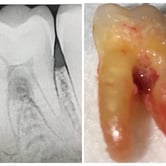

Pulpitis Crónica Hiperplásica

La pulpitis crónica hiperplásica es una inflamación de la pulpa con crecimiento excesivo de tejido pulpar a través de una caries abierta.

Los pacientes notan un tejido rojo que sobresale de la cavidad dental.

El tratamiento incluye la eliminación del tejido afectado y un tratamiento de conducto. Es crucial tratar la caries para evitar infecciones adicionales.